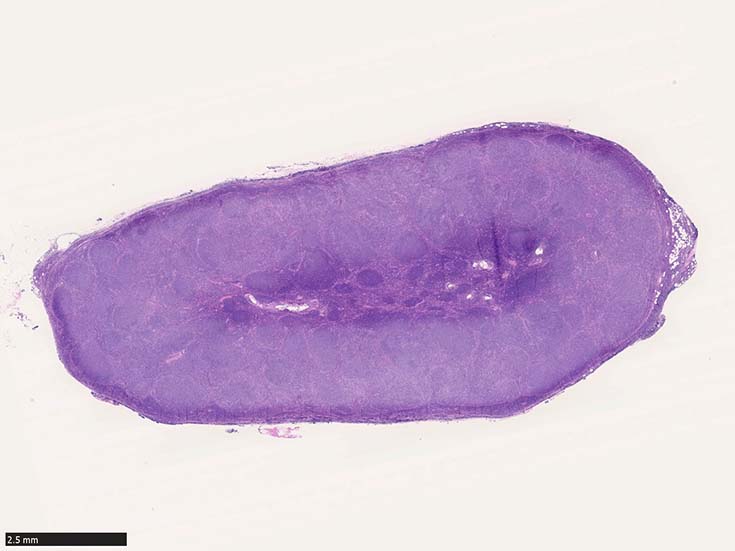

濾胞増殖pattern

腫瘍細胞のほとんどがcentrocyteであっても右図のようにcentroblastを超えるような大型細胞が1個でもあれば,他に大型細胞のみからなる腫瘍性胚中心がないかと,より注意して観察するようにしています。

ほぼすべてがcentroblast/largetransformed cellからできあがっている腫瘍性胚中心があれば,low-grade componentだけではなく,high-grade component(grade 3B)が存在するという診断になります (Dr竹内賢吾談--許可を得て先生の文章をそのままパクり)

低倍率像で濾胞は濾胞間組織にくらべ明るくみえる症例がほとんど。これは小型リンパ球よりやや大型で蒼白な腫瘍細胞が増殖するため。

濾胞が濾胞間組織より暗く見えるreverse patternの症例が認められる。

腫瘍性濾胞は均等にリンパ節全体に分布する。辺縁洞は閉塞され,時に被膜外へ浸潤する。